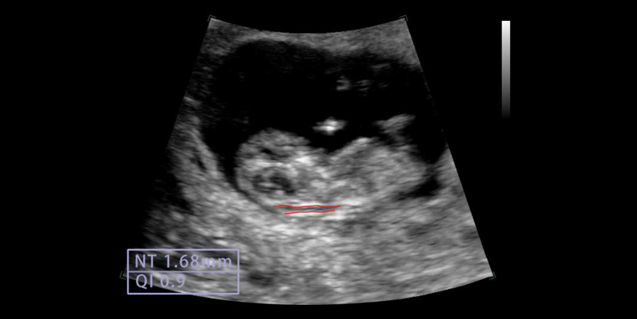

临床图像